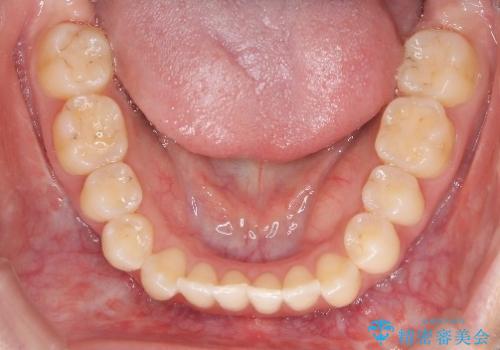

再矯正 前歯のガタツキをマウスピース矯正で治療したい

- 前に矯正治療をしたが、後戻りしてガタツキが出てきたので、治したいとのことで来院されました。

ワイヤー治療とマウスピース矯正、2通りの治療を提案させていただき、マウスピース矯正治療を希望されましたので、インビザラインによる治療を開始しました。